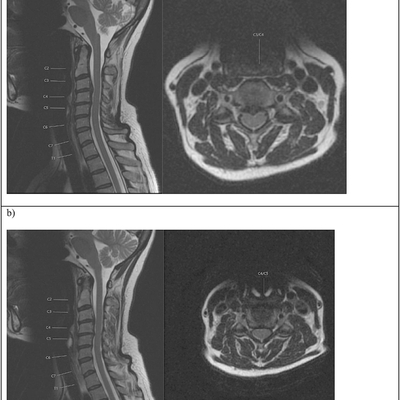

Click on an image below to view more info.